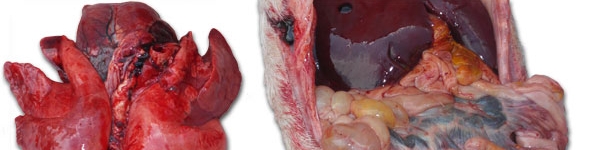

A necropsia mostrou em todos os casos uma grave congestão pulmonar e enterite de gravidade variável com uma afecção de mais ou menos importância dos gânglios linfáticos mesentéricos.

O resultado do laboratório em relação com o envio de amostras de 10 de Julho mostra, como no primeiro caso, enterite, linfoadenite e congestão pulmonar. Isolou-se Streptococcus suis do cérebro de um porco e do endocárdio de outro.